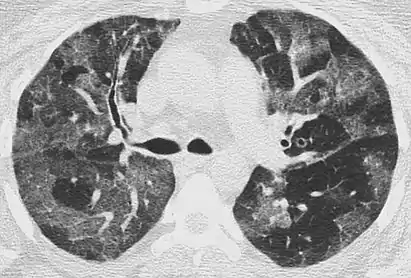

High-Resolution CT image in a patient with Pneumocystis pneumonia infection showing ground-glass opacities.

Inflammation and fibrosis can also cause diffuse GGOs. Pneumocystis pneumonia, an infection typically seen in immunocompromised (e.g. patients with AIDS) or immunosuppressed individuals, is a classic cause of diffuse GGOs. Many viral pneumonias and idiopathic interstitial pneumonias can also lead to a diffuse GGO pattern. Radiation pneumonitis, a side effect of pulmonary radiation therapy, can lead to pulmonary fibrosis and diffuse GGOs.[6]